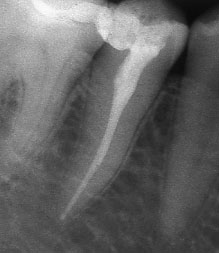

При добре проведено ендодонтско лечение кореновият канал е запълнен точно до стеснението, разположено на 1 - 1.5 мм. от края на канала - т.нар. физиологично стеснение. Не бива да остава незапълнена част от канала. Много често се получава припресване на канлопълнежното средство извън канал на зъба, в тъканите около корена.

Ако при диагностична рентгенография се установи, че даден канал не е запълнен до физиологичното стеснение, е необходимо да се проведе повторно ендодонтско лечение.